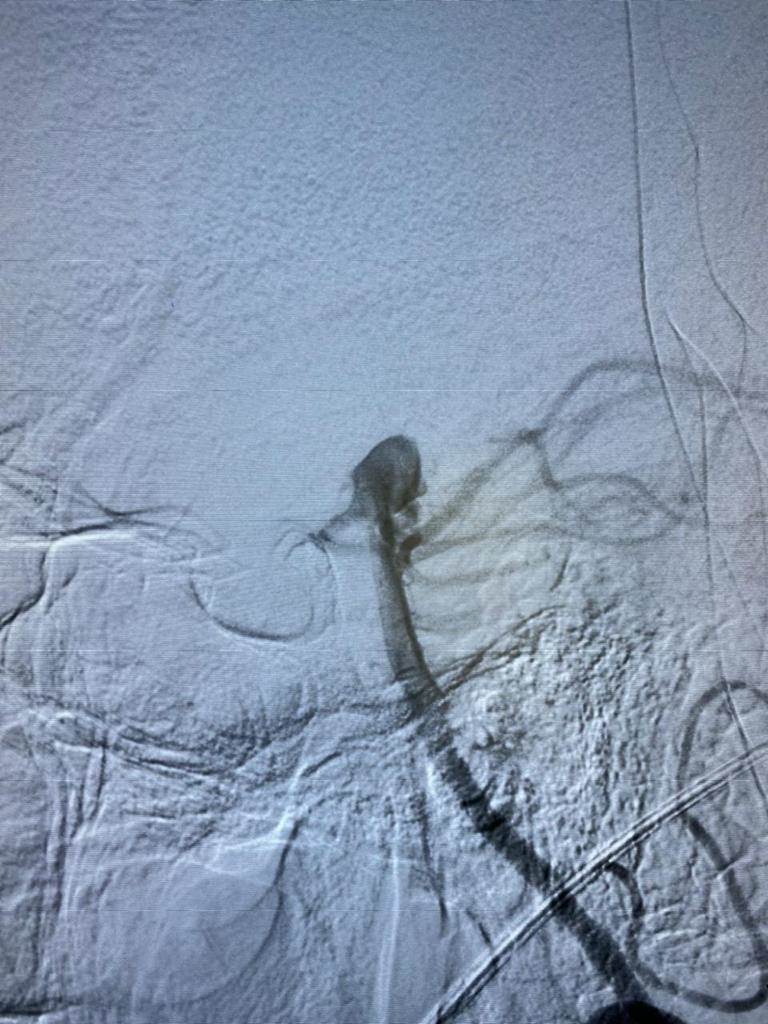

وأضافت الهيئة ،أنه تم عمل الفحوصات الطبية المريضة التي تبلغ من العمر ٥٠ عام فور دخولها مستشفى النصر التخصصي، وتبين أنها تعاني من تمدد شرياني بالشريان القاعدي بالمخ ، وعليه تم إجراء القسطرة التشخيصية المخية للمريضة ووضع الخطة العلاجية لها على يد الأستاذ الدكتور أحمد بسيوني، استشاري القسطرة المخية بمستشفيات هيئة الرعاية الصحية ببورسعيد، وهي الآن تحت الملاحظة وحالتها مستقرة.

وتابع أ.د. أحمد بسيوني أستاذ المخ والأعصاب وقسطرة المخ بطب عين شمس، والمشرف على القسطرة المخية بمستشفيات هيئة الرعاية الصحية ببورسعيد، أن هذا الإجراء يأتي ضمن حزمة من الإجراءات المنوط بها قسم طب المخ والأعصاب بمستشفيات هيئة الرعاية الصحية ببورسعيد برئاسة الاستاذ الدكتور هاني عارف، لافتًا إلى الخدمات العلاجية التي تقدمها وحده السكتة الدماغية وإذابة الجلطات المخيه في زمن قياسي، والذي سيسهم في تقليل معدلات الوفيات والإعاقه للمواطن البورسعيدي، فضلًا عن الاختبارات الفسيولوجية لمرضي المخ والأعصاب، وعلاج مرضي التصلب المتناثر، ومجموعة كبيرة من الخدمات الأخري التي تضمن حصول المواطن البورسعيدي علي الخدمة الأمثل، والتي تضاهي في جودتها أعظم المراكز العالمية وداخل المحافظة دون تحمل مشقة السفر والعناء من أجل توافر الخدمة.